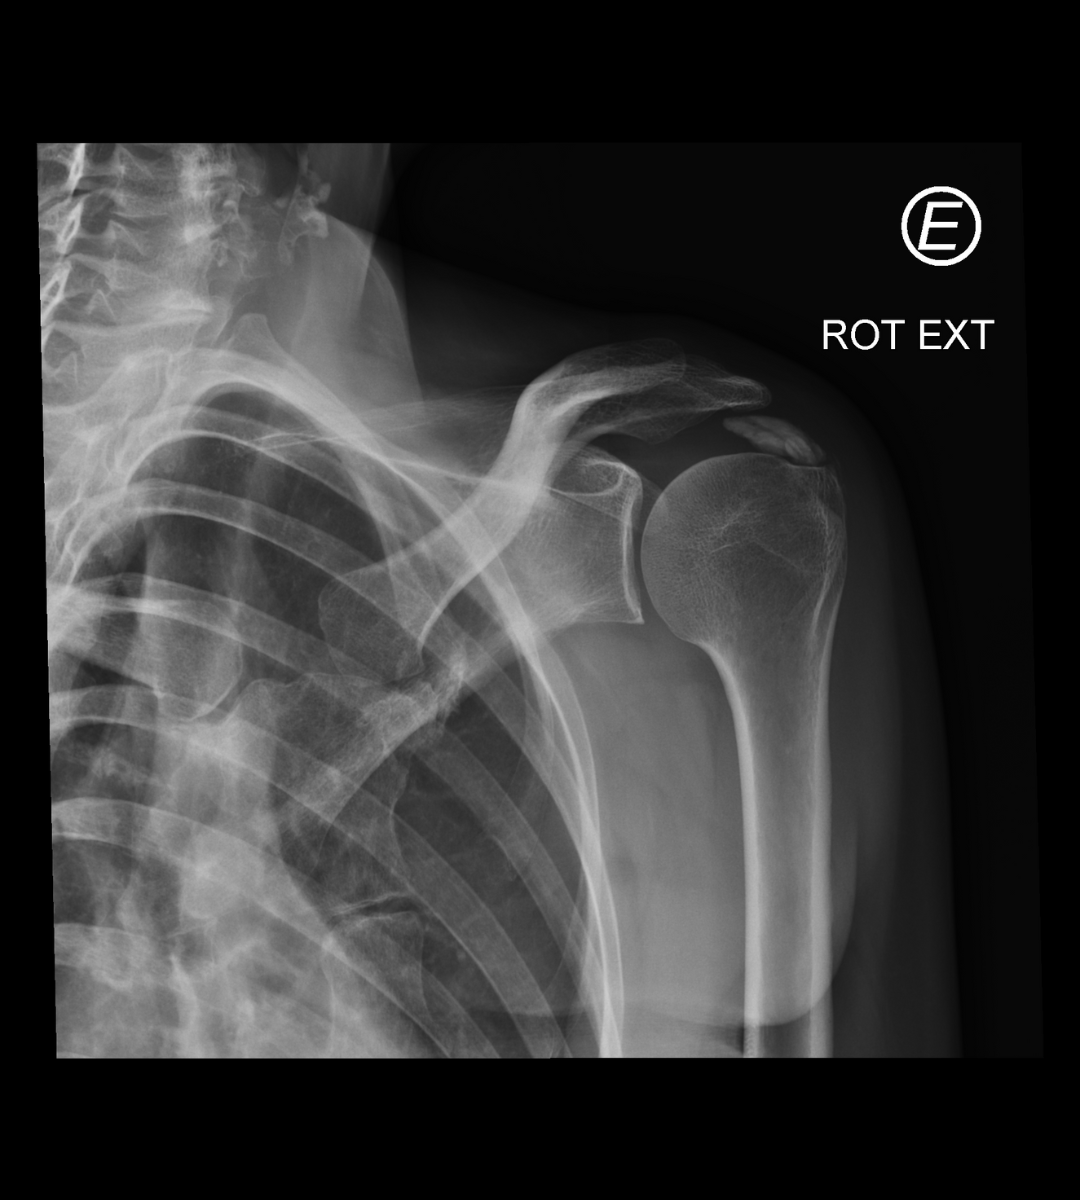

Depois dessa conversa inicial, o próximo passo é o exame físico. O médico vai movimentar seu braço em diferentes posições para ver quais movimentos desencadeiam a dor e onde ela é mais intensa. Ele pode pressionar certas áreas do ombro também. E para ter certeza absoluta, a radiografia (o raio-X) é quase sempre o exame principal. É nessa imagem que as famosas calcificações no tendão aparecem bem visíveis, confirmando o diagnóstico. Às vezes, se houver alguma dúvida, pode ser solicitado um ultrassom, que mostra os tecidos moles com mais detalhes.

A confirmação vem com a imagem certa, mostrando aquelas calcificações que causam a inflamação e a dor no ombro. É importante não se desesperar ao ouvir o diagnóstico. O tratamento para a dor no ombro por tendinite calcária existe e pode trazer muito alívio. Vamos combinar, ninguém merece ficar com dor, né? Buscar ajuda médica logo no início faz toda a diferença.